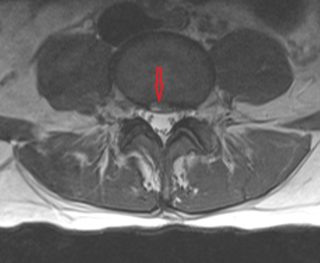

HIZ Lesion axial

HIZ lesion, Axia